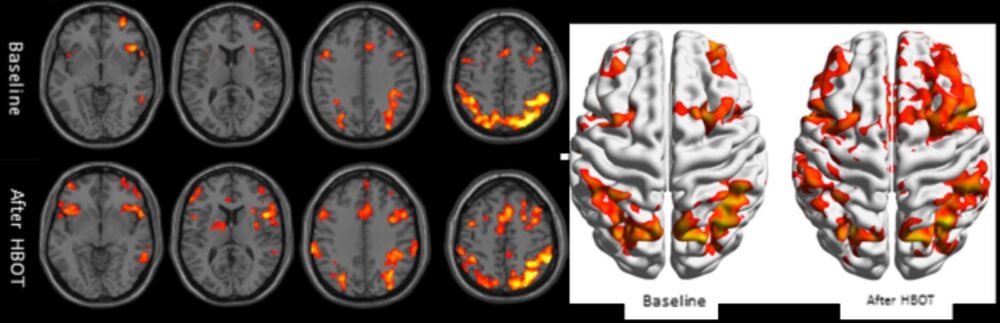

“Moreover, both functional and structural improvement was observed in the non-healing brain wounds that characterize PTSD,” she said.

“With the new HBOT protocols, we can activate mechanisms that repair the wounded brain tissue. The treatment induces reactivation and proliferation of stem cells, as well as generation of new blood vessels and increased brain activity, ultimately restoring the functionality of the wounded tissues,” said Efrati.